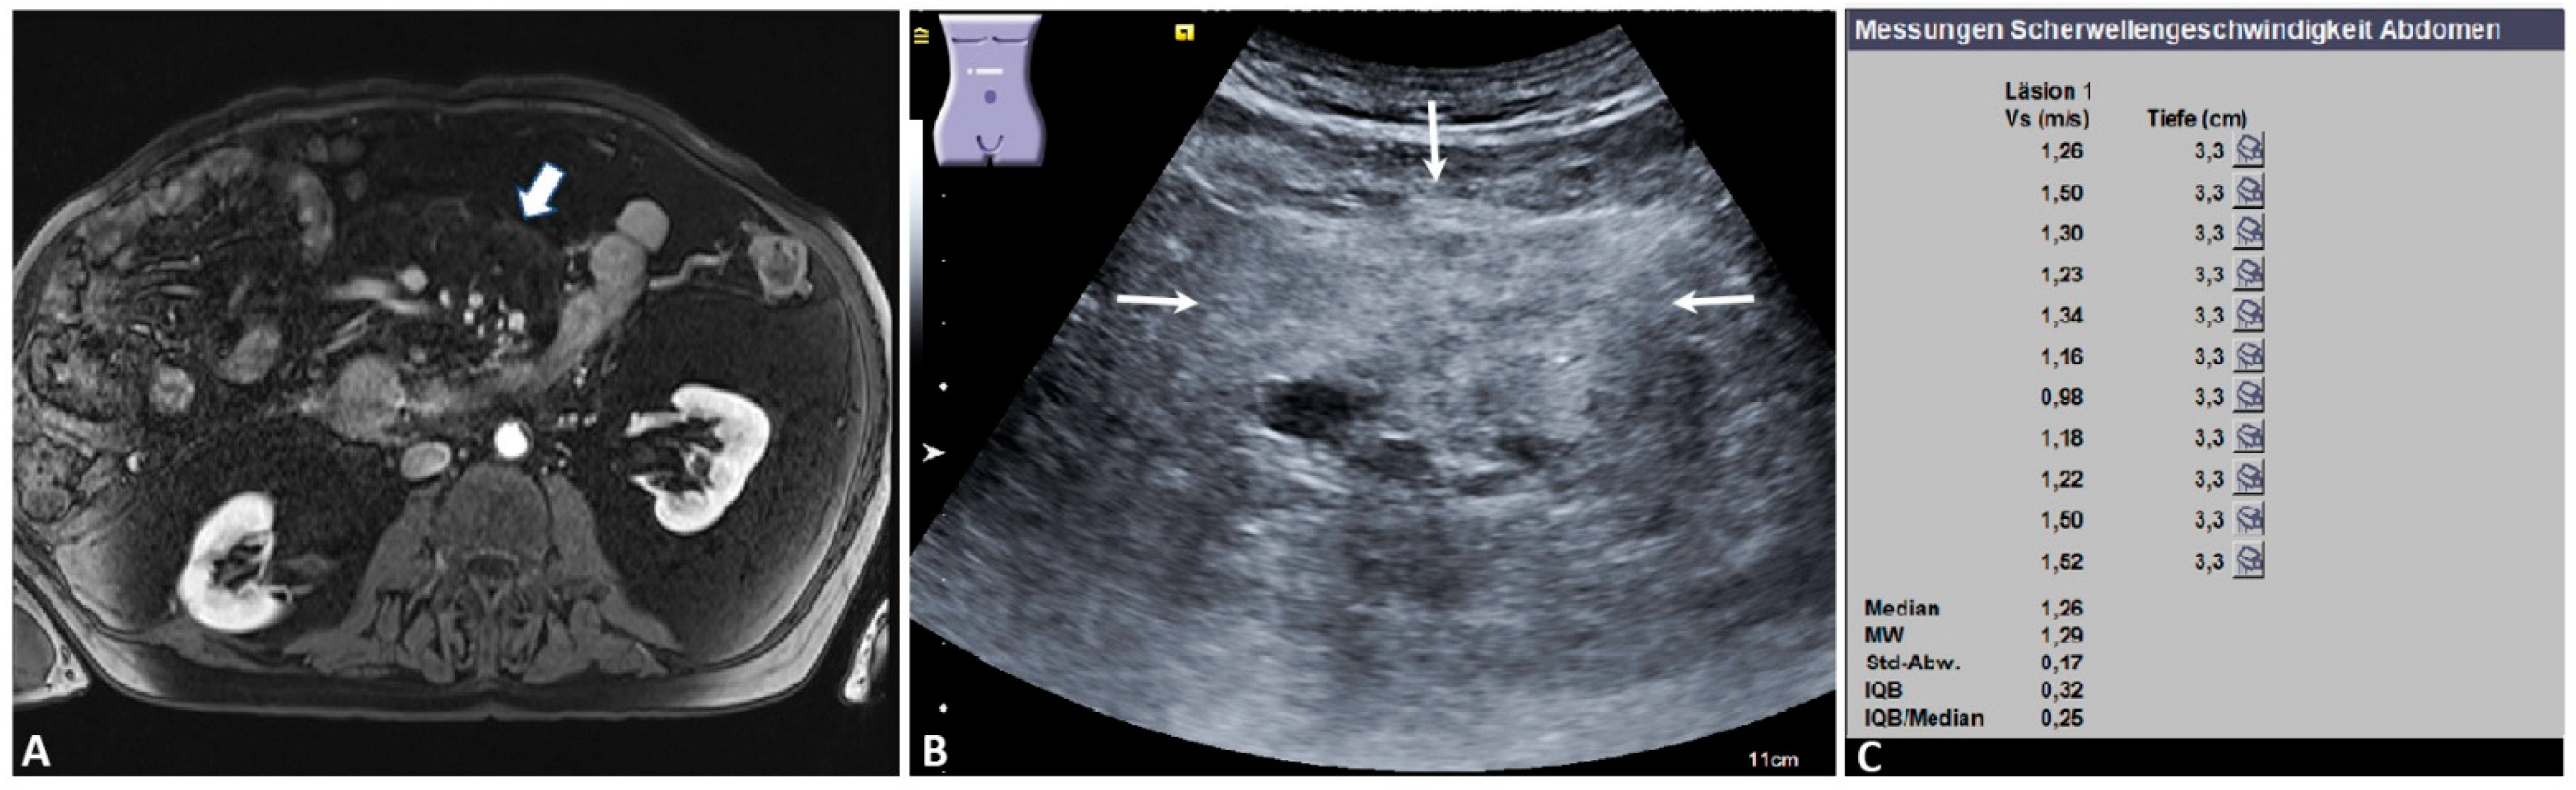

| bMMs | 37 | 1.59 ± 0.93 | 0.59 | 3.62 | 4.75 ± 1.20 |

| Mesenteritis | 26 | 1.75 ± 1.02 | 0.59 | 3.62 | 4.53 ± 0.99 |